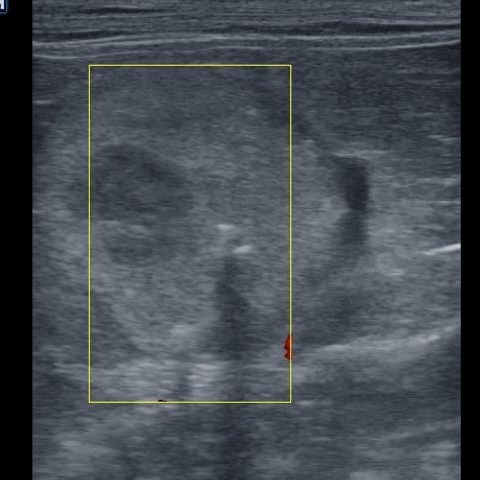

Dato che questi risultati hanno escluso alcune malattie (insufficienza renale e diabete, per esempio) ma non ci hanno indicato una patologia specifica, è stata effettuata una ecografia dell’addome. Da questa è risultato che è presente una massa abbastanza grande vicino al rene sinistro (foto in basso), compatibile, per la sua posizione, con la ghiandola surrenale sinistra. La ghiandola surrenale destra non era invece visibile. Questo quadro ecografico ci porta a sospettare la presenza di un tumore della ghiandola surrenale sinistra secernente cortisolo, che ha portato Maya ad avere la sindrome di Cushing.